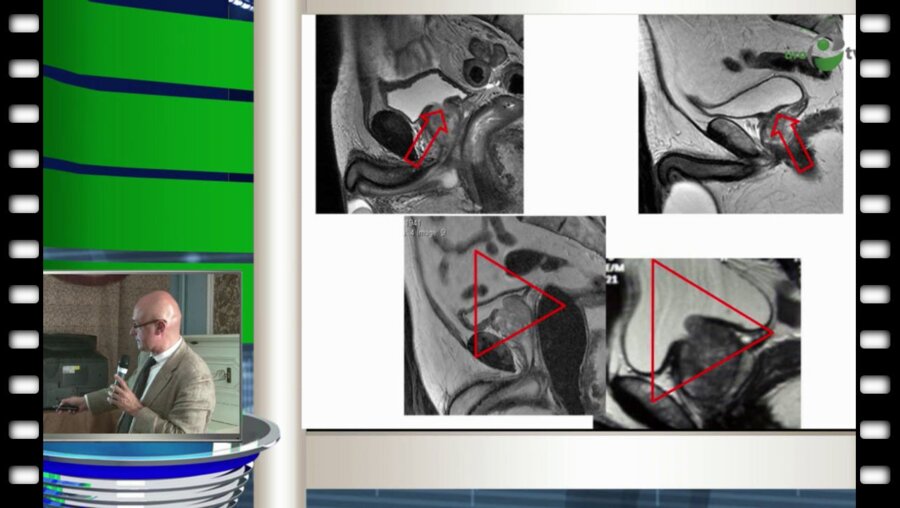

Фундаментальная андрология: наука + практика. Выпуск 4. Спермограмма: читаем между строк. Часть 2